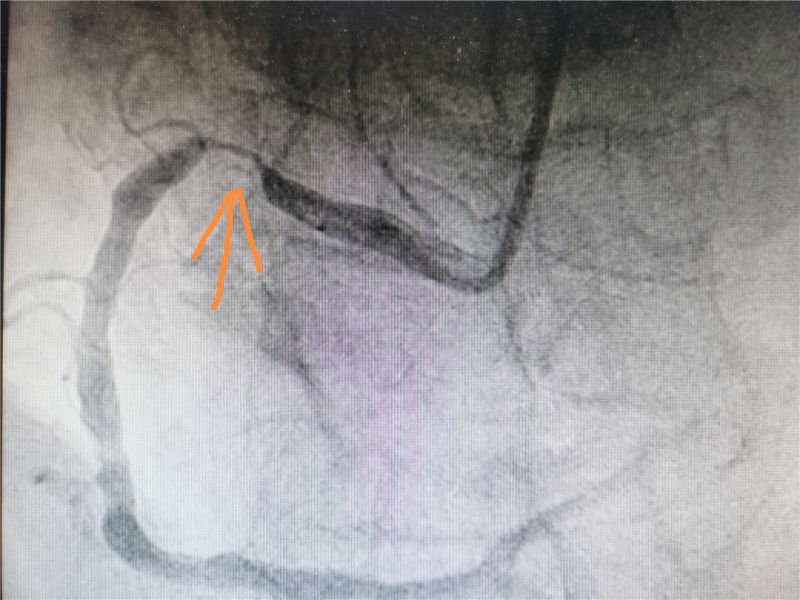

手术过程中,行冠脉造影可见患者右冠近端弥漫狭窄,最重95%,予以狭窄处植入一枚3.5mm*23mm可降解支架。可降解支架较目前主流的金属支架通过性差,较难通过病变,另外需要充分贴合血管壁避免支架内血栓的形成,因此在技术及经验等方面对术者要求较高。在宇大伟及其团队的精准实施和密切配合下,手术历时半个小时,患者冠状动脉血管恢复正常,无不良反应,手术圆满成功。

术前